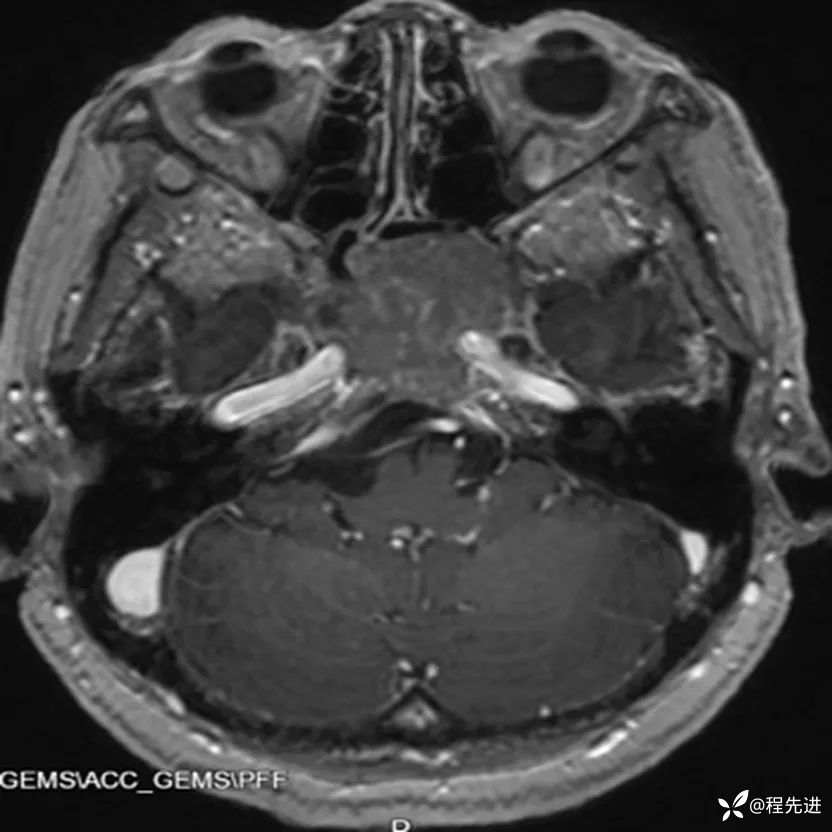

患者性别:女

患者年龄:63岁

简要病史:外伤检查发现颅底占位

CT增强:

MRI平扫+增强: